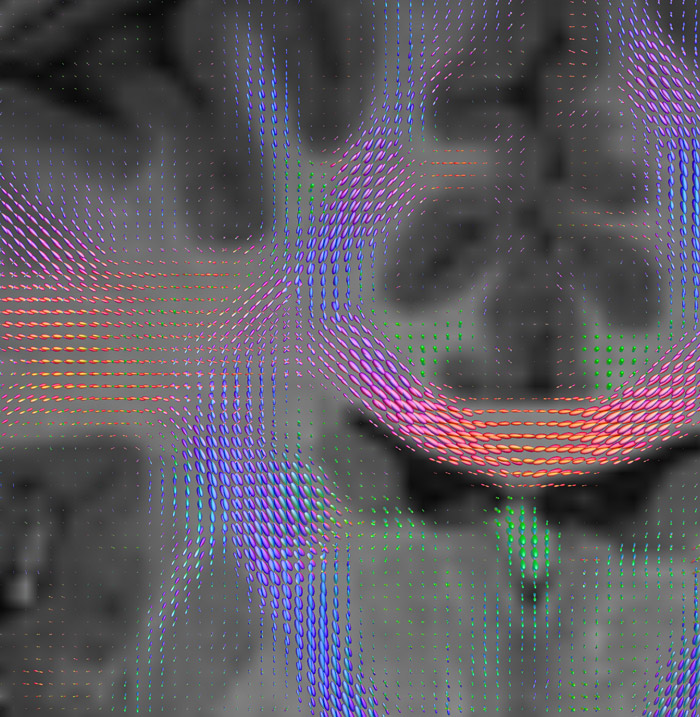

CSD of multishell DWI results in the white matter FOD at each voxel. Unlike the conventional diffusion tensor model, this approach enables accurate modeling of multiple fiber populations within a single voxel.

Crossings of the corpus callosum, corticospinal tracts, and the superior longitudinal fasciculus are shown.

Crossing fibers of the corpus callosum bordered by the superior longitudinal fasciculus as well as within in the pons.